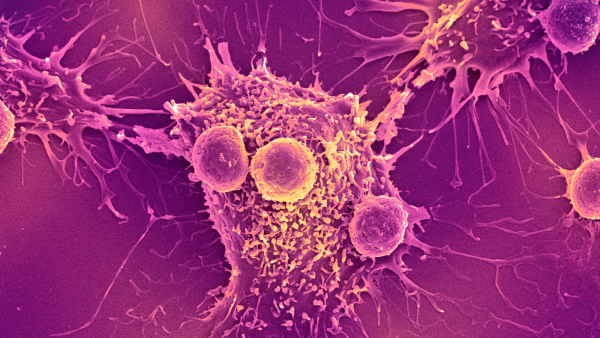

Нове дослідження показує, що тепер можливо розводити мишей із повністю розвиненою та функціональною імунною системою людини. (Зображення: Evgenyi_Eg via Getty Images)

Стикаючись з інфекцією, ці «гуманізовані» миші виробляють імунні клітини, що імітують структуру та різноманітність імунних клітин, що виробляються людьми. Дослідники виявили, що коли їм вводять хімічну речовину, яка викликає поширене запалення в організмі, у мишей розвивається варіант аутоімунного захворювання – вовчака, який дуже схожий на той, що спостерігається у людей.

Це не перші гуманізовані миші, яких коли-небудь виводили — лабораторні тварини є основними в дослідженнях, оскільки вони дозволяють вченим вивчати особливості імунної системи людини всередині живої тварини. Це корисно для перевірки безпеки та ефективності нових ліків, а також вакцин проти інфекційних захворювань, перш ніж їх випробовуватимуть на людях.

Після введення людського естрогену миші почали виробляти безліч людських імунних клітин. Серед них були Т-клітини, які безпосередньо атакують мікроби, та В-клітини, що виробляють антитіла, що знищують бактерії та допомагають позначити патогени для знищення.